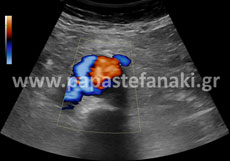

Με την έγχρωμη υπερηχοτομογραφία (Triplex) μπορούμε να ελέγχουμε την ροή του αίματος μέσα στα αγγεία του σώματος όπως η αορτή, οι καρωτίδες, οι νεφρικές αρτηρίες, οι φλέβες και αρτηρίες άνω και κάτω άκρων